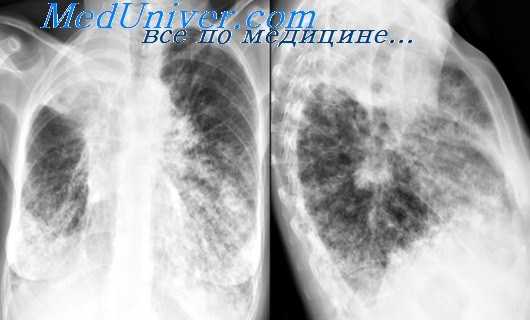

Осумкованный плеврит – локальное скопление экссудата, ограниченное плевральными сращениями от остальной плевральной полости. В зависимости от локализации и объема экссудата клиническая картина варьирует от бессимптомного течения до выраженных проявлений, включающих боли в грудной клетке, одышку, кашель, затруднение глотания. Диагноз осумкованного плеврита выставляется на основании результатов рентгенографии легких, КТ грудной клетки, УЗИ плевральной полости, торакоцентеза. Лечение осумкованного плеврита зависит от его этиологии, которая устанавливается после исследования экссудата (антибиотикотерапия, противотуберкулезная терапия, по показаниям – хирургическое вмешательство).

Для первичного выявления осумкованного плеврита чрезвычайно важны данные полипозиционой рентгенографии грудной клетки (в прямой, боковых и косых проекциях) и рентгеноскопии легких. Рентгенологически осумкование проявляется в виде затемнения характерной локализации и формы. В сложных случаях для дифференциальной диагностики требуется наложении искусственного пневмоторакса и пневмоперитонеума, проведение КТ легких. Длительное существование осумкованного плеврита может отразиться на состоянии легочной паренхимы. Поэтому для оценки изменений прилежащих отделов легкого (бронхов, сосудов) используются рентгеноконтрастные исследования - бронхография и ангиопульмонография.

- Рентген. Полипозиционная рентгенография и рентгеноскопия легких при эмпиеме плевры обнаруживают интенсивное затенение. Для уточнения размеров, формы осумкованной эмпиемы плевры, наличия свищей выполняют плеврографию с введением водорастворимого контраста в плевральную полость. Для исключения деструктивных процессов в легких показано проведение КТ, МРТ легких.